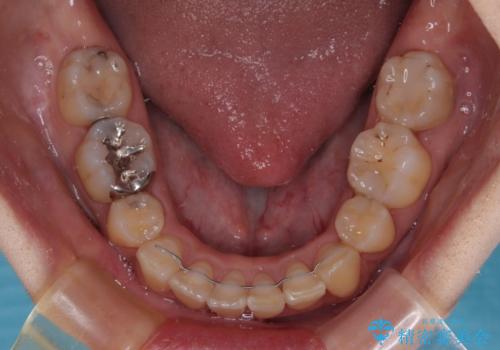

どこまで口元の突出感を改善できるのか不安でしたが、舌のトレーニングをしっかりと行ってくださり、我々も驚くほど劇的に改善することができました。